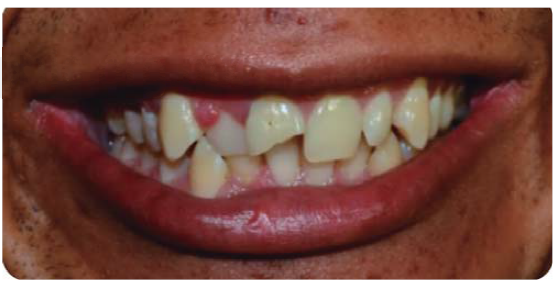

Paciente masculino de 21 años de edad, sano, presentando LDT al caer de una bicicleta; con fractura coronaria complicada de los dientes: 12, 11 y 21, con una evolución de 48 horas (Figura 1).

Debido a la evolución de dos días desde el accidente, el paciente presenta dolor e inflamación a la exploración extraoral, durante la exploración intraoral se observa la exposición pulpar de los dientes involucrados (Figura 2) e indica el tratamiento de urgencia a seguir, para disminuir el dolor e inflamación.

Paciente de sonrisa gingival que presenta fractura complicada de corona del diente 21 en el tercio medio coronal (Figura 3) y del diente 12 en el tercio cervical (Figura 4), fractura complicada de corona y raíz del diente 11 (Figura 5); gingivitis inducida por placa dentobacteriana (Figura 7), trasposición de los dientes 13 y 14, anodoncia verdadera de los dientes 15, 35 y 45, presentando los dientes temporales 55, 75 y 85.